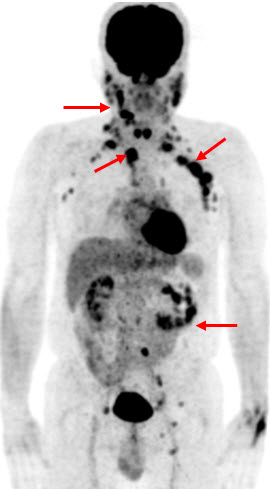

Hình 1. Bệnh nhân Vũ D.L., nam, 56 tuổi. Chẩn đoán: Non Hodgkin Lymphoma , GPB: WF7. Hình PET/CT toàn thân thấy tổn thương hạch ở nhiều vị trí: vùng cổ, trung thất, hố nách, ổ bụng, bẹn (các mũi tên) tăng hấp thu FDG.